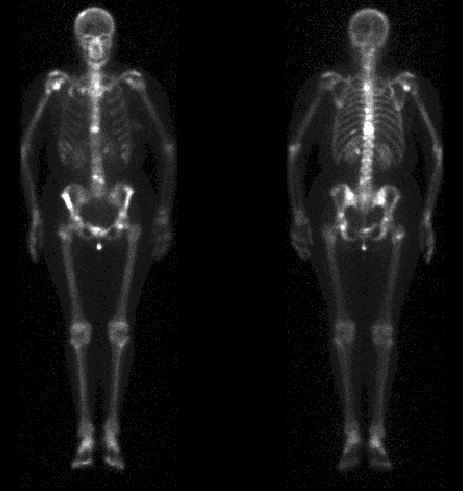

Depistarea prezenţei metastazelor osoase, mai ales în cancerele pulmonare, mamare şi prostată, reprezintă cea mai frecventă indicaţie a scintigrafiei osoase, deoarece nu există altă metodă de detecţie mai rapidă şi ieftină. Scintigrafia este uşor de realizat, sensibilă şi fără contraindicaţii şi deosebit de utilă pentru stadializarea afecţiunii, mai ales ţinând cont că circa 30% dintre pacienţi au deja metastaze osoase în momentul diagnosticului. Scintigrafic, metastazele osoase vor apărea ca multiple focare, hipercaptante diseminate la nivelul întregului schelet. Multe dintre leziuni sunt nevizualizabile pe imaginile radiografice, cu o simptomatologie minimă, scintigrafia permiţând astfel detectarea acestora cu mult timp înainte de a fi vizualizate radiografic.